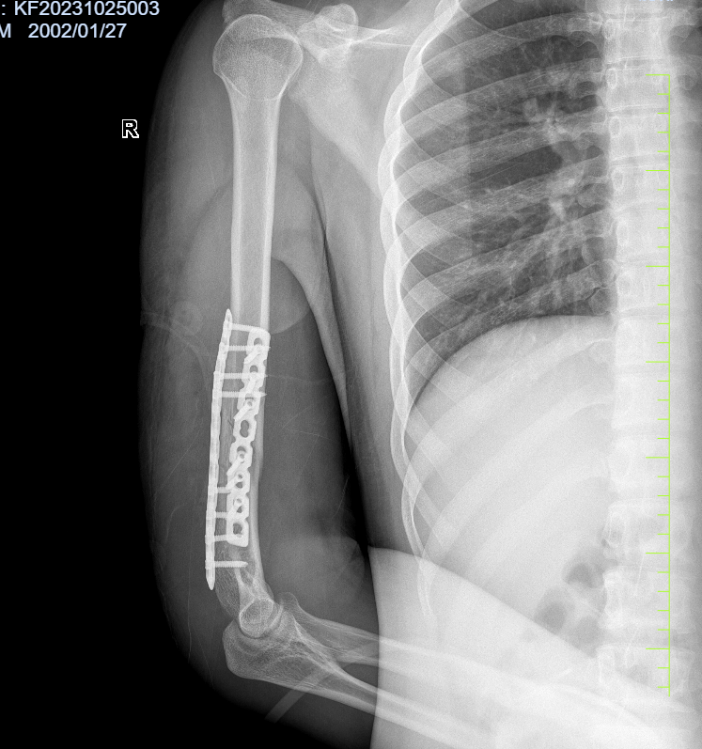

病例四:患者,男,21岁,因“与他人掰腕致右上肢疼痛伴活动受限5小时”入院。诊断:右肱骨干粉碎性骨折,桡神经损伤;行右肱骨干骨折切开复位内固定+桡神经探查修复术;手术顺利,术后进行康复训练中,功能恢复良好。

右肱骨干粉碎性骨折 术后 X线片